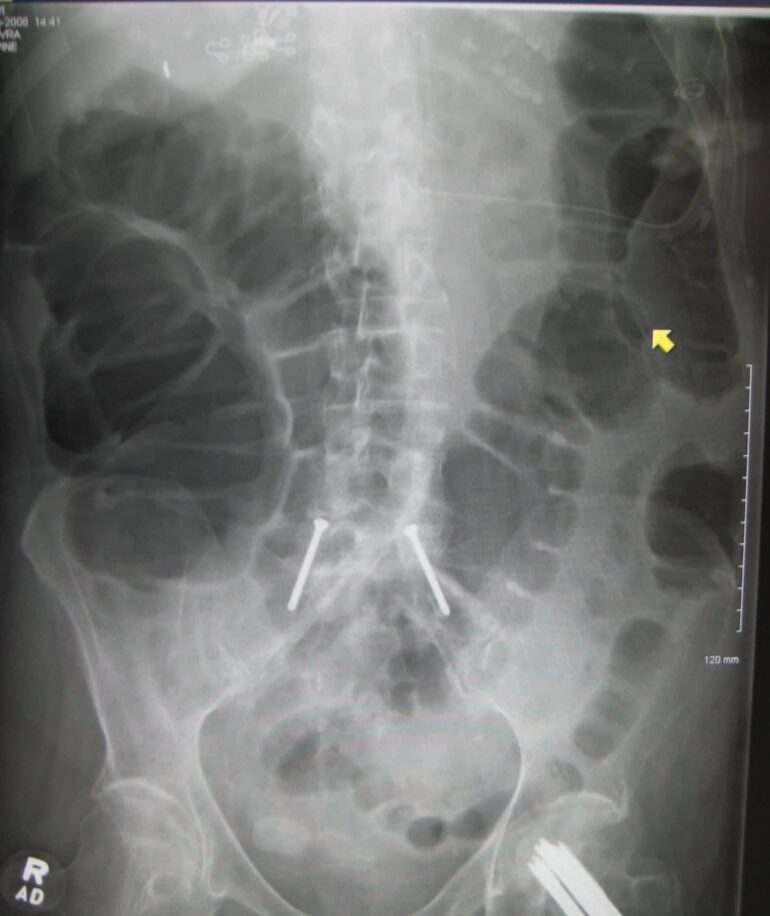

9

Q

what does this AXR show?

A

bowel perforation

- Rigler’s sign = both sides of bowel wall are visible

- gas below diaphragm